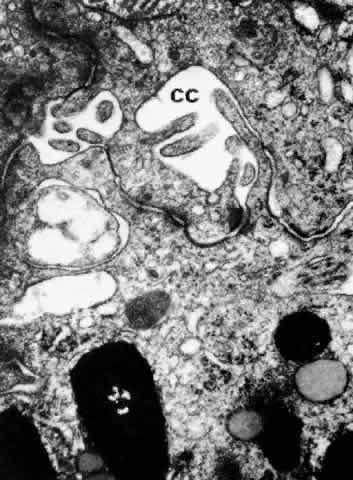

Another unusual structural differentiation between NPE and PE cells is the “ciliary channel,”16 (Fig. 23) an explanation for which has not yet been offered. These channels are small foci of dilated intercellular space that often contain fine granular material and have microvilli from the cell surfaces protruding into them.

Fig. 23. Ciliary channels (CC) between the pigmented and nonpigmented epithelium in the anterior pars plicata. Microvilli from the cell surfaces extend into these spaces. (X 35,000)